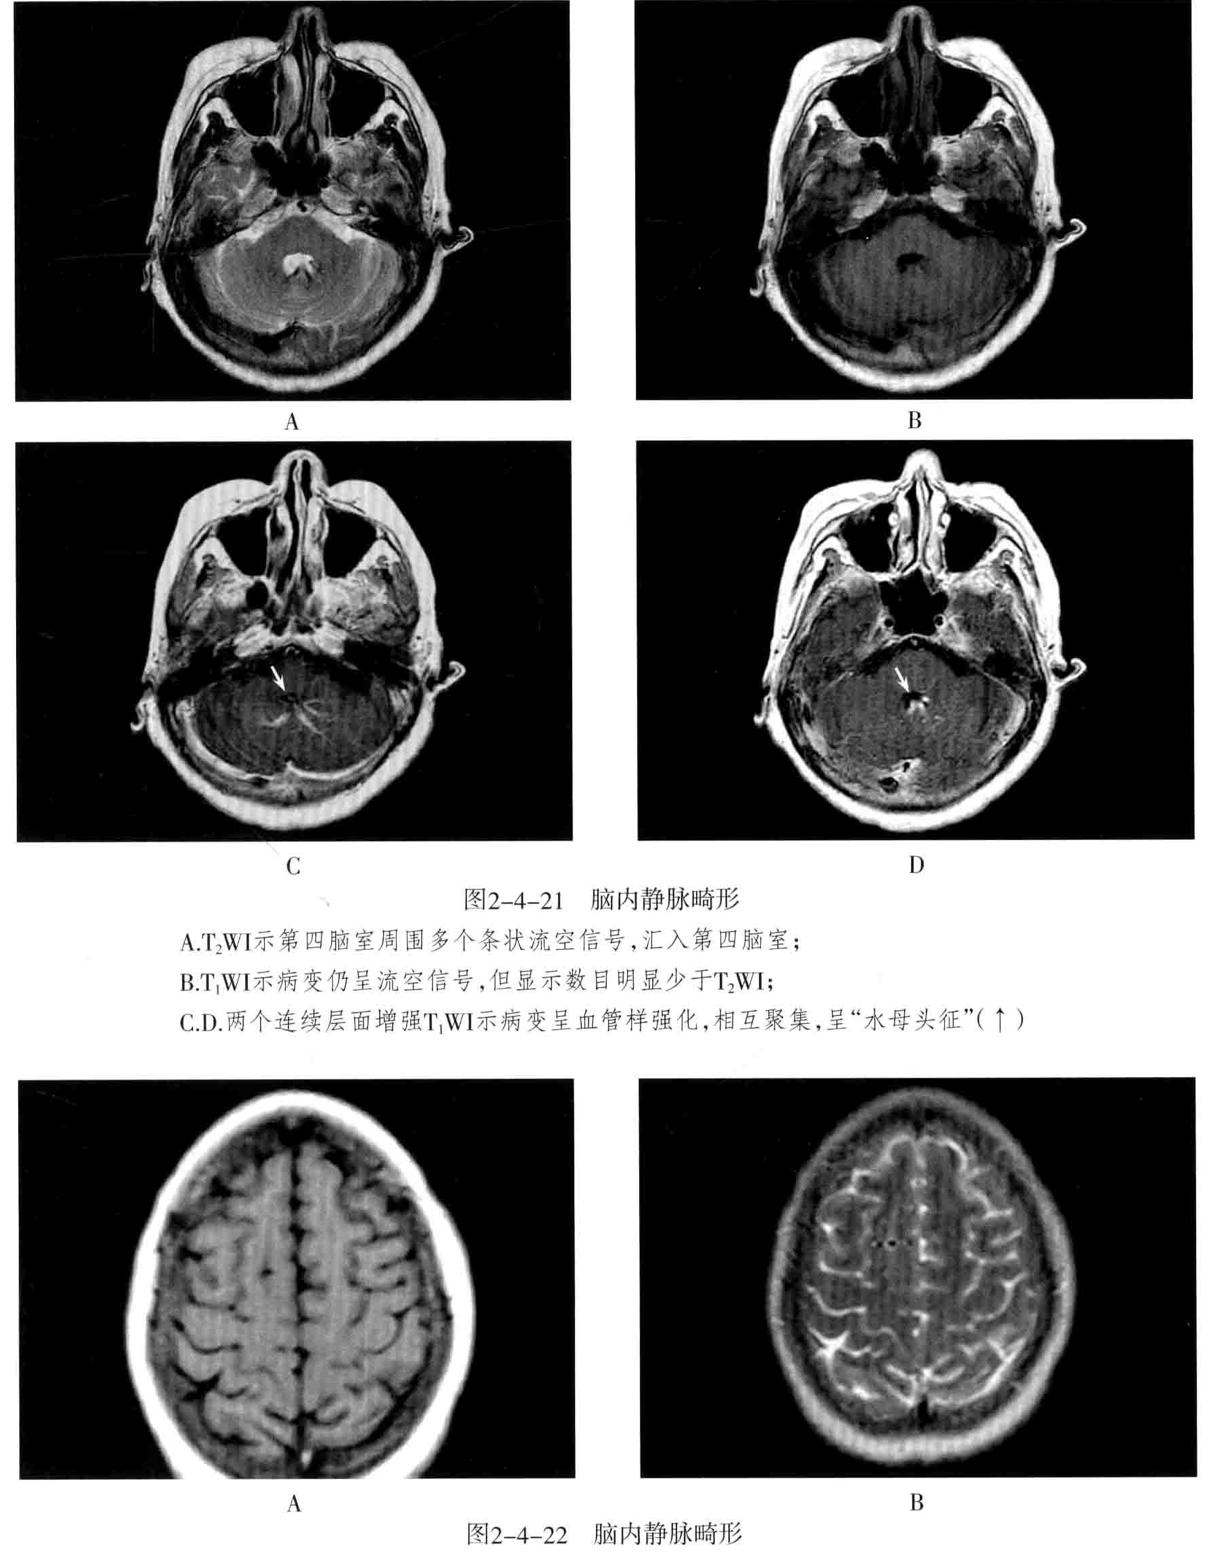

- 脑静脉性血管瘤 极为少见。静脉性血管瘤是一种组织上完全由静脉成分构成的脑血管畸形,任何年龄均可见,病理特点为许多放射状排列的扩张髓静脉连接成一条或多条扩张的经皮质或室管膜下引流静脉,最后汇入静脉窦。常发生于 额叶及小脑,以第四脑室周围多见 ,常伴发其他血管畸形,最常见为海绵状血管瘤。

- CT表现:平扫显示不清,周围无脑水肿,有时可见出血等改变,CTA典型表现为额叶或小脑许多细小髓静脉放射状汇入一条或几条引流静脉,最后汇入静脉窦,呈“水母头征”。

- MRI表现:可因病灶大小及血流速度不同而在MRI上呈多种信号,T1WI、T2WI多呈流空信号,少数由于血流缓慢也可呈略高信号,FLAIR呈低信号。增强后髓静脉及引流静脉明显强化,典型者呈“水母头征”,引流静脉可走向脑表面而引流至静脉窦,或走向脑室引流至室管膜静脉。MRV可显示引流静脉及其引流情况,但不显示髓静脉,SWI序列对本病显示很敏感。病灶周围无脑水肿表现,有时可见出血。